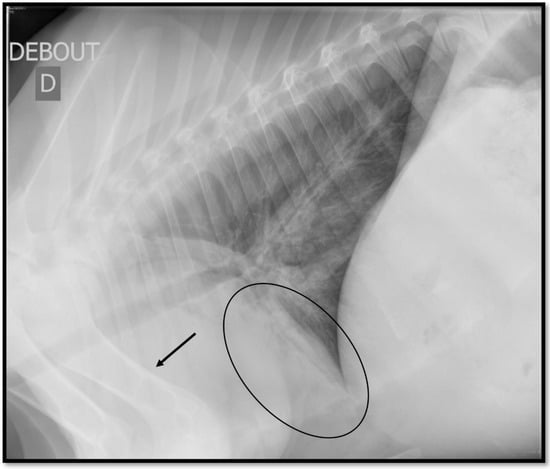

Several patterns could be visualized on TR during BP: bronchial pattern, when there are prominent and/or thickened bronchial walls; interstitial pattern, when there is a diffuse increased opacity of the lung parenchyma causing loss of definition of the vascular structures; and alveolar pattern, when the lung presents a soft tissue opacity that completely obscures the identification of the vascular structures, borders of the heart, or diaphragm; and nodular pattern, when there are one or more soft tissue opacity structures measuring up to 3 cm in diameter. Pleural effusion and pneumothorax are also easily visualized on TR [,,,]. Among those lesions, the alveolar pattern is the most present lesion during BP (Figure 3) [,,,].

Figure 3.

Image of an alveolar pattern on thoracic ultrasonography (circle). The alveoli are filled by an inflammatory material, either tumoral or cicatricial. An area of soft-tissue opacity is present, hiding the pulmonary vessels and the structures in the mediastinum like the cardiac borders. One of the drawbacks of thoracic radiography is the anatomical superimposition, which can hide or be confused with an alveolar pattern like the superimposition of the forelimbs (arrow).

The alveolar pattern can, however, be confused with the superimposed anatomic structures, especially because of the forelegs when the calf is standing [,]. This could lead to a false positive diagnosis (calves do not actually have any lesions), impacting the Sp of the test []. Extending the forelegs forward or adding DV or VD views can limit those superimposition issues [,,]. Unlike TUS, the interpretation of BP lesions on TR is not simple for practitioners. Their detection and interpretation need experts []. To universalize its use by practitioners in the field, a simplification of its interpretation is needed.